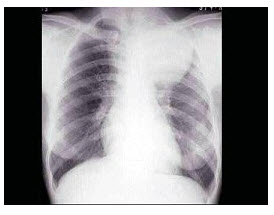

13、单项选择题

患者,女,28岁,轻咳两月,有盗汗。胸片如图:

本例最可能的诊断为()

A.过敏性肺炎

B.嗜酸性肉芽肿

C.支气管扩张

D.肺隔离症

E.肺结核

点击查看答案